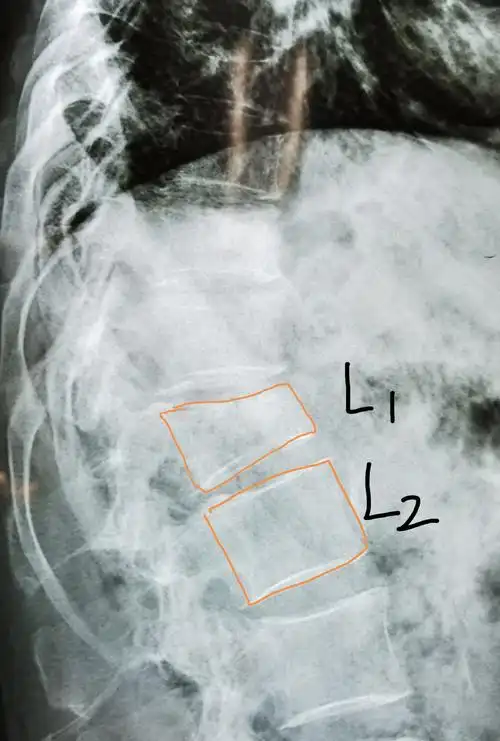

腰椎平片提示腰1椎体前缘压缩有二分之一,侧位片非常明显,且腰椎ct